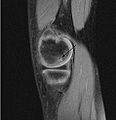

Magnetic resonance imaging (MRI) is useful for staging OCD lesions, evaluating the integrity of the joint surface, and distinguishing normal variants of bone formation from OCD by showing bone and cartilage edema in the area of the irregularity. MRI provides information regarding features of the articular cartilage and bone under the cartilage, including edema, fractures, fluid interfaces, articular surface integrity, and fragment displacement.[37][38] A low T1 and high T2 signal at the fragment interface is seen in active lesions. This indicates an unstable lesion or recent microfractures.[30] While MRI and arthroscopy have a close correlation, X-ray films tend to be less inductive of similar MRI results.[38]